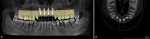

A 65-year-old male patient presented for a comprehensive examination and expressed interest in improving his smile. He stated that his "front teeth are too big and long." He also commented on his lack of gum display. Radiographs were taken, and it was noted that teeth Nos. 8 through 10 had prior endodontic treatment, and single crowns were present on teeth Nos. 6 and 9 through 11. A ceramic three-unit bridge was present on teeth Nos. 6 through 8 (Figure 1). The connector between Nos. 6 and 7 was fractured. A large post was noted in tooth No. 8 with no evident tooth structure coronally, and there appeared to be restorative material around the coronal aspect of the post. A fracture was noted on tooth No. 10 at the apical end of the post present in the tooth. The patient was scheduled to return to discuss a treatment plan after evaluation of the clinical findings.

The patient returned to review the proposed treatment plan. Tooth No. 8, one of the abutment supports of the ceramic bridge on Nos. 6 through 8, had a fracture at the gingival margin (Figure 2). The treatment plan was discussed and would include aligner orthodontics to open the vertical dimension of occlusion (VDO), as the bite had collapsed over time, and achieve proper canine guidance. Extraction of the residual root at No. 8 along with extraction of teeth Nos. 9 and 10 would be performed, with placement of a provisional bridge at Nos. 6 through 11 during treatment. Implants would be placed at sites Nos. 7 through 10.